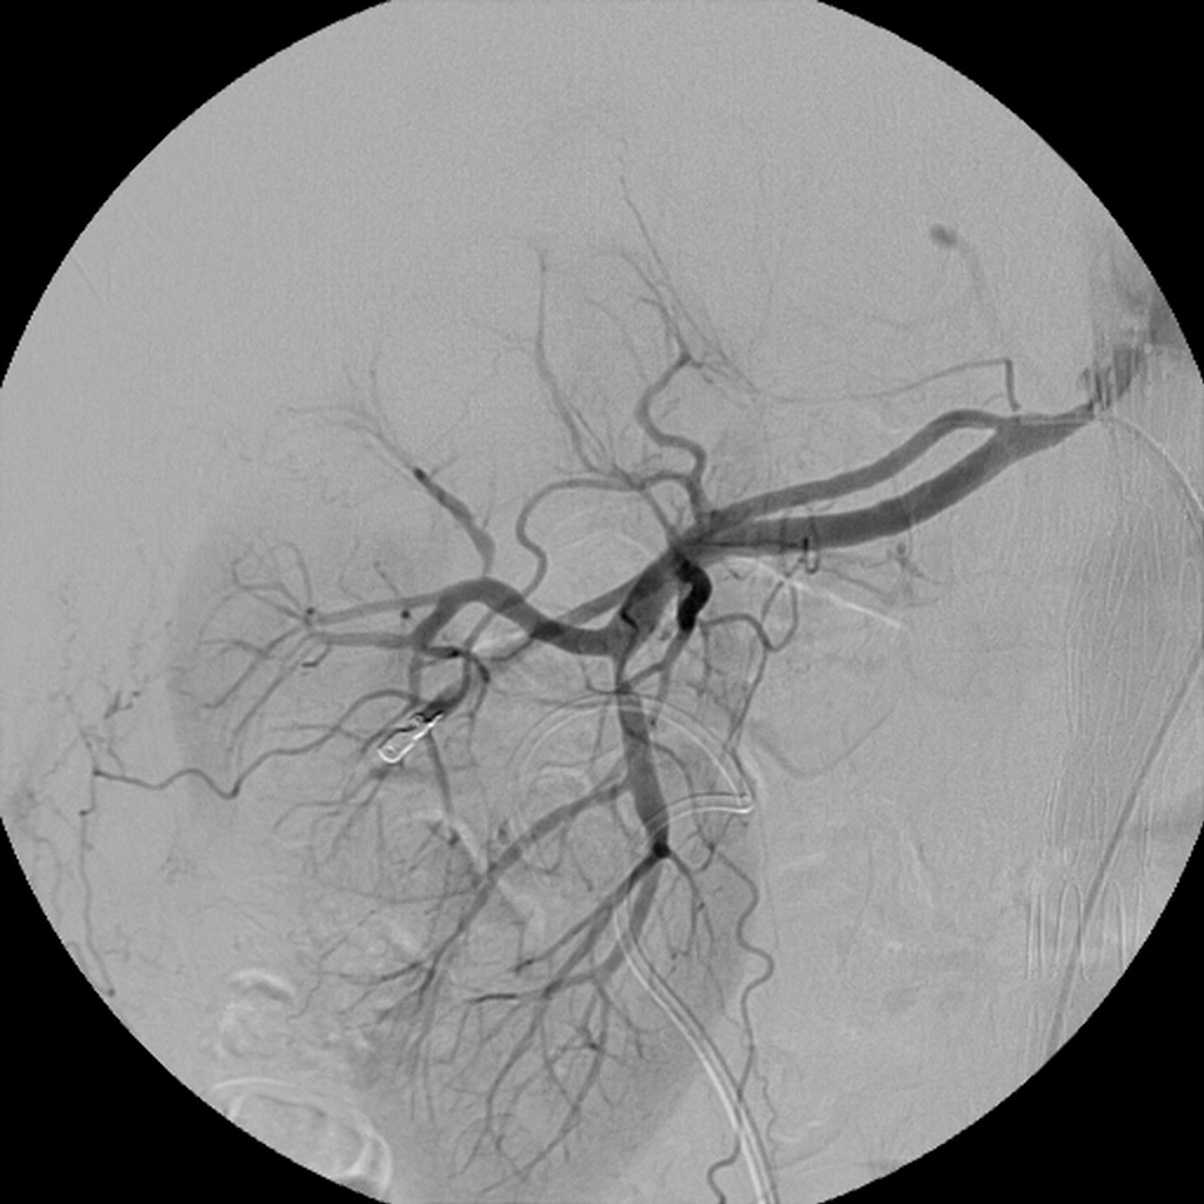

Хирургические процессы при эмболизации гемангиомы на фото

Раздел: Снимки-откровения